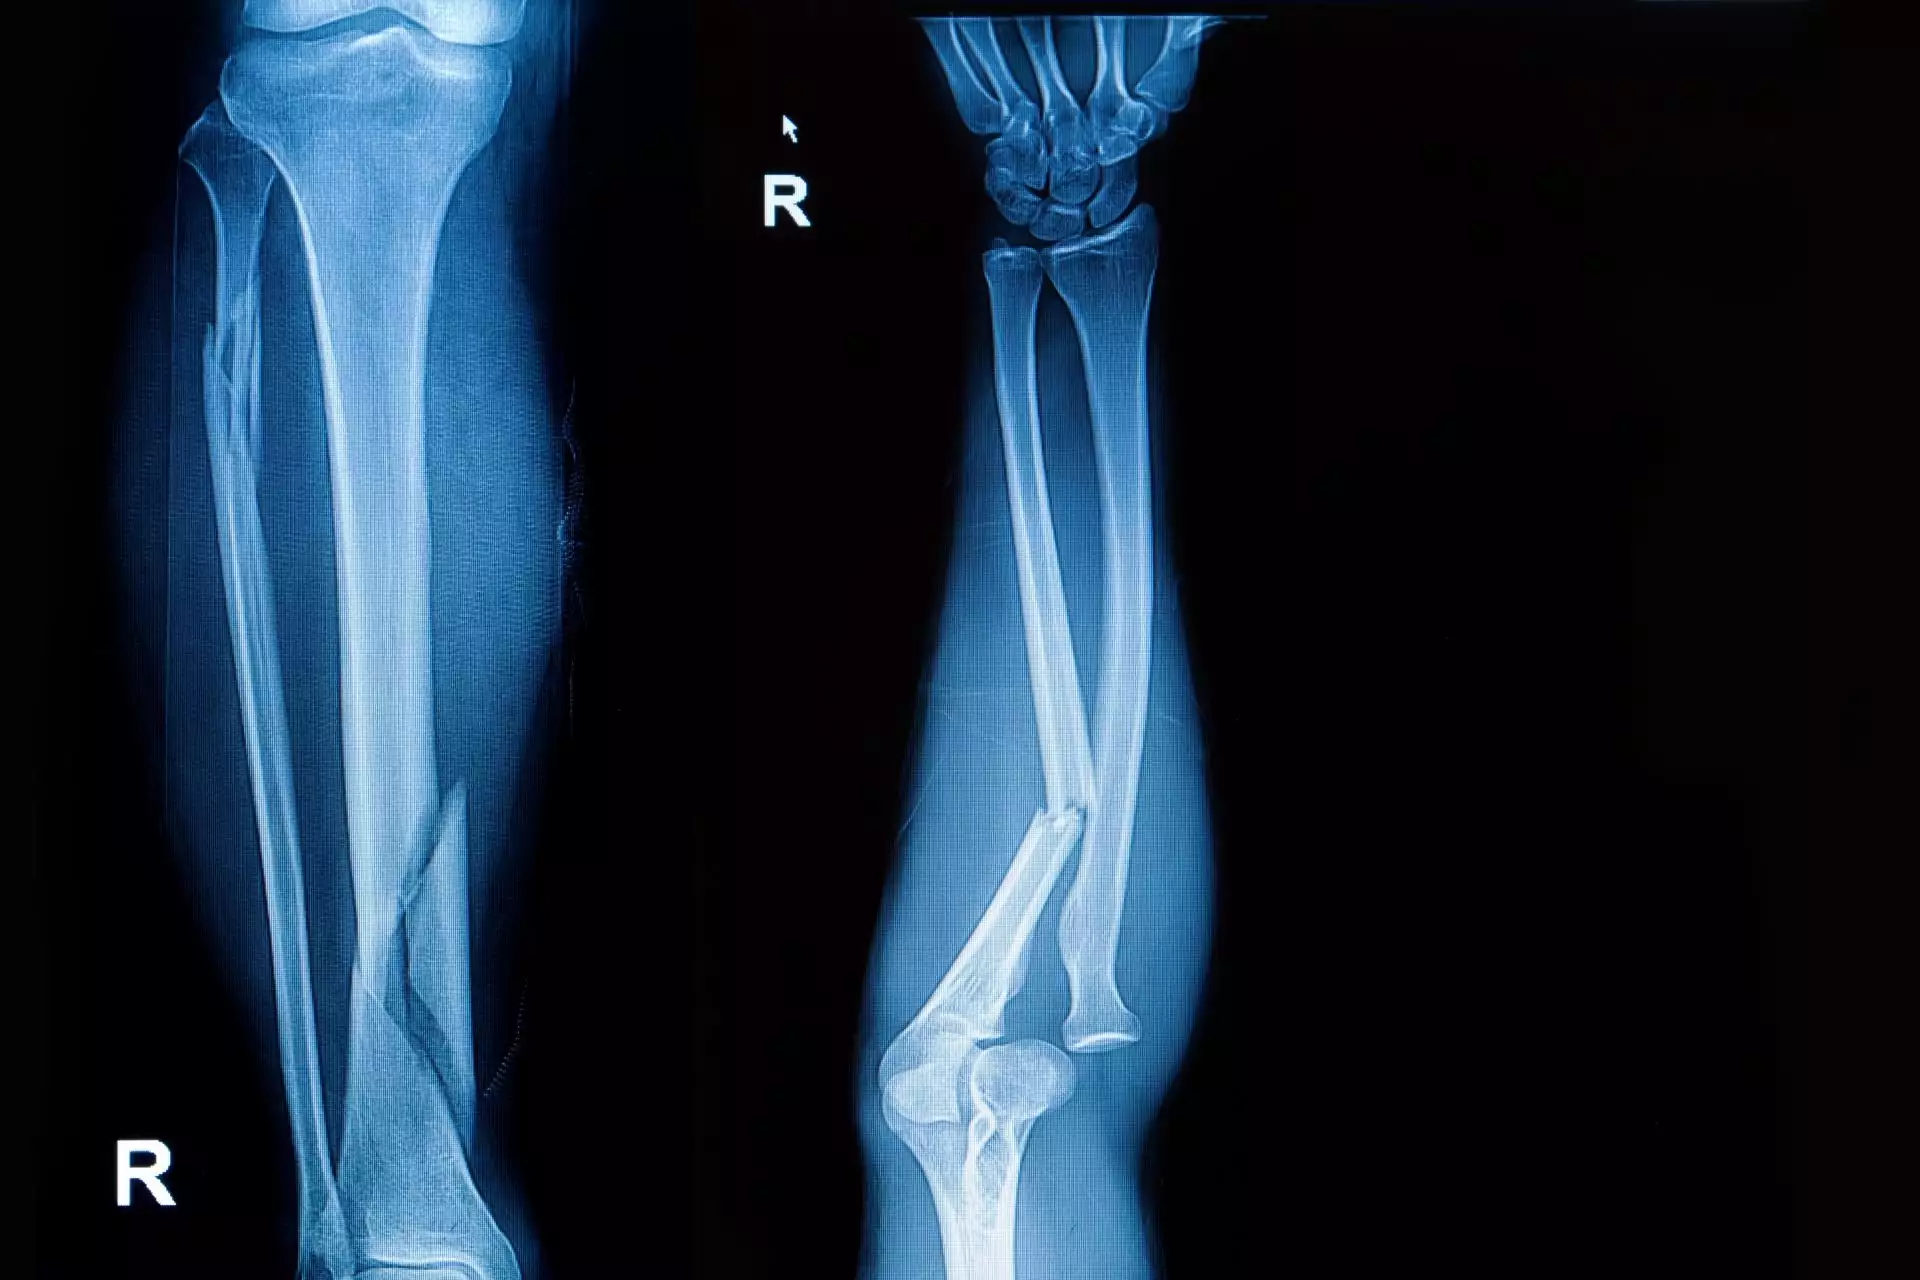

Druhým nejčastějším typem zranění je zlomenina. Při pádu máme tendenci pod tělo nastavit ruce, které tak přicházejí do kontaktu s vozovkou jako první a tlumí náraz. Ten ale kosti nevydrží a pod enormním tlakem se zlomí. Často lékaři musí pacienty operovat, zejména pokud utrpí otevřenou zlomeninu, která se bez lékařského zásahu nezahojí.